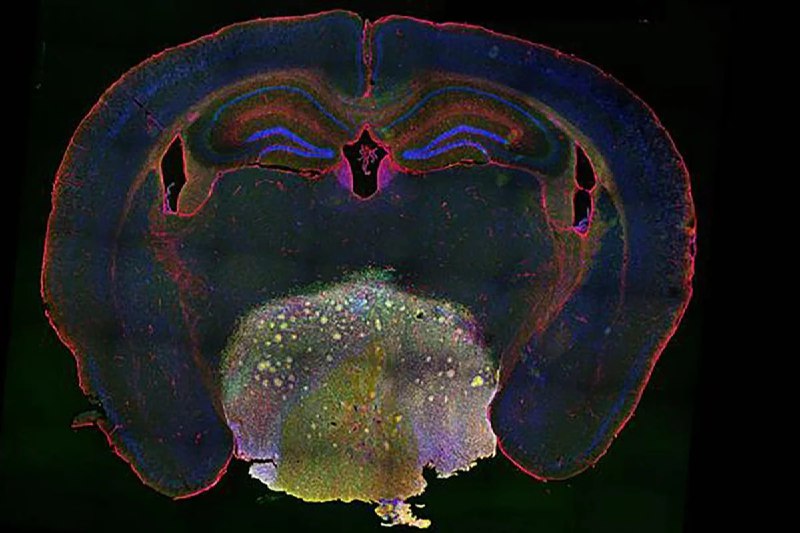

ΠΡΠ΅ΠΏΠ°ΡΠ°Ρ (S)-Π°ΠΌΠ»ΠΎΠ΄ΠΈΠΏΠΈΠ½ Π±Π΅Π·ΠΈΠ»Π°Ρ, ΠΊΠΎΡΠΎΡΡΠΉ ΠΎΠ±ΡΡΠ½ΠΎ ΠΈΡΠΏΠΎΠ»ΡΠ·ΡΠ΅ΡΡΡ Π΄Π»Ρ Π»Π΅ΡΠ΅Π½ΠΈΡ Π³ΠΈΠΏΠ΅ΡΡΠΎΠ½ΠΈΠΈ, ΠΏΠΎΠΊΠ°Π·Π°Π» ΡΡΡΠ΅ΠΊΡΠΈΠ²Π½ΠΎΡΡΡ Π² Π±ΠΎΡΡΠ±Π΅ Ρ ΡΠ΅Π΄ΠΊΠΎΠΉ Π΄ΠΎΠ±ΡΠΎΠΊΠ°ΡΠ΅ΡΡΠ²Π΅Π½Π½ΠΎΠΉ ΠΎΠΏΡΡ ΠΎΠ»ΡΡ ΠΌΠΎΠ·Π³Π° β ΠΊΡΠ°Π½ΠΈΠΎΡΠ°ΡΠΈΠ½Π³ΠΈΠΎΠΌΠΎΠΉ. ΠΡΠ° ΠΎΠΏΡΡ ΠΎΠ»Ρ ΠΏΠΎΡΠ°ΠΆΠ°Π΅Ρ Π³ΠΈΠΏΠΎΡΠ°Π»Π°ΠΌΡΡ ΠΈΠ»ΠΈ Π³ΠΈΠΏΠΎΡΠΈΠ·, Π²ΡΠ·ΡΠ²Π°Ρ Π΄ΠΈΠ°Π±Π΅Ρ, ΠΎΠΆΠΈΡΠ΅Π½ΠΈΠ΅, ΠΏΡΠΎΠ±Π»Π΅ΠΌΡ ΡΠΎ Π·ΡΠ΅Π½ΠΈΠ΅ΠΌ ΠΈ Π½Π°ΡΡΡΠ΅Π½ΠΈΠ΅ Π³ΠΎΡΠΌΠΎΠ½ΠΎΠ².

Π£ΡΠ΅Π½ΡΠ΅ ΠΈΠ·ΡΡΠΈΠ»ΠΈ Π±ΠΎΠ»Π΅Π΅ 3 ΡΡΡ. ΡΠΎΠ΅Π΄ΠΈΠ½Π΅Π½ΠΈΠΉ ΠΈ Π²ΡΠ±ΡΠ°Π»ΠΈ (S)-Π°ΠΌΠ»ΠΎΠ΄ΠΈΠΏΠΈΠ½ Π±Π΅Π·ΠΈΠ»Π°Ρ β ΡΡΡΠ΅ΠΊΡΠΈΠ²Π½ΡΠΉ, Π±Π΅Π·ΠΎΠΏΠ°ΡΠ½ΡΠΉ ΠΈ Π΄ΠΎΡΡΡΠΏΠ½ΡΠΉ ΠΏΡΠ΅ΠΏΠ°ΡΠ°Ρ. ΠΠ½ Π±Π»ΠΎΠΊΠΈΡΡΠ΅Ρ ΠΊΠ°Π»ΡΡΠΈΠ΅Π²ΡΠ΅ ΡΠΈΠ³Π½Π°Π»Ρ Π² ΠΊΠ»Π΅ΡΠΊΠ°Ρ ΠΎΠΏΡΡ ΠΎΠ»ΠΈ ΠΈ Π½Π°ΡΡΡΠ°Π΅Ρ ΠΈΡ Π²Π·Π°ΠΈΠΌΠΎΠ΄Π΅ΠΉΡΡΠ²ΠΈΠ΅ Ρ Π½Π΅ΠΉΡΠΎΠ½Π°ΠΌΠΈ, ΡΡΠΎ ΠΏΡΠΈΠ²ΠΎΠ΄ΠΈΡ ΠΊ ΡΠ΅Π³ΡΠ΅ΡΡΠΈΠΈ ΠΎΠΏΡΡ ΠΎΠ»ΠΈ.

Π Π΅Π·ΡΠ»ΡΡΠ°ΡΡ ΠΈΡΡΠ»Π΅Π΄ΠΎΠ²Π°Π½ΠΈΡ ΠΎΠΏΡΠ±Π»ΠΈΠΊΠΎΠ²Π°Π½Ρ Π² ΠΆΡΡΠ½Π°Π»Π΅ Science Translational Medicine. Π£ΡΠ΅Π½ΡΠ΅ ΠΏΠ»Π°Π½ΠΈΡΡΡΡ Π½Π°ΡΠ°ΡΡ ΠΊΠ»ΠΈΠ½ΠΈΡΠ΅ΡΠΊΠΈΠ΅ ΠΈΡΠΏΡΡΠ°Π½ΠΈΡ, ΡΡΠΎΠ±Ρ ΠΏΠΎΠ΄ΡΠ²Π΅ΡΠ΄ΠΈΡΡ Π΄Π΅ΠΉΡΡΠ²ΠΈΠ΅ ΠΏΡΠ΅ΠΏΠ°ΡΠ°ΡΠ° Π½Π° ΠΏΠ°ΡΠΈΠ΅Π½ΡΠ°Ρ .